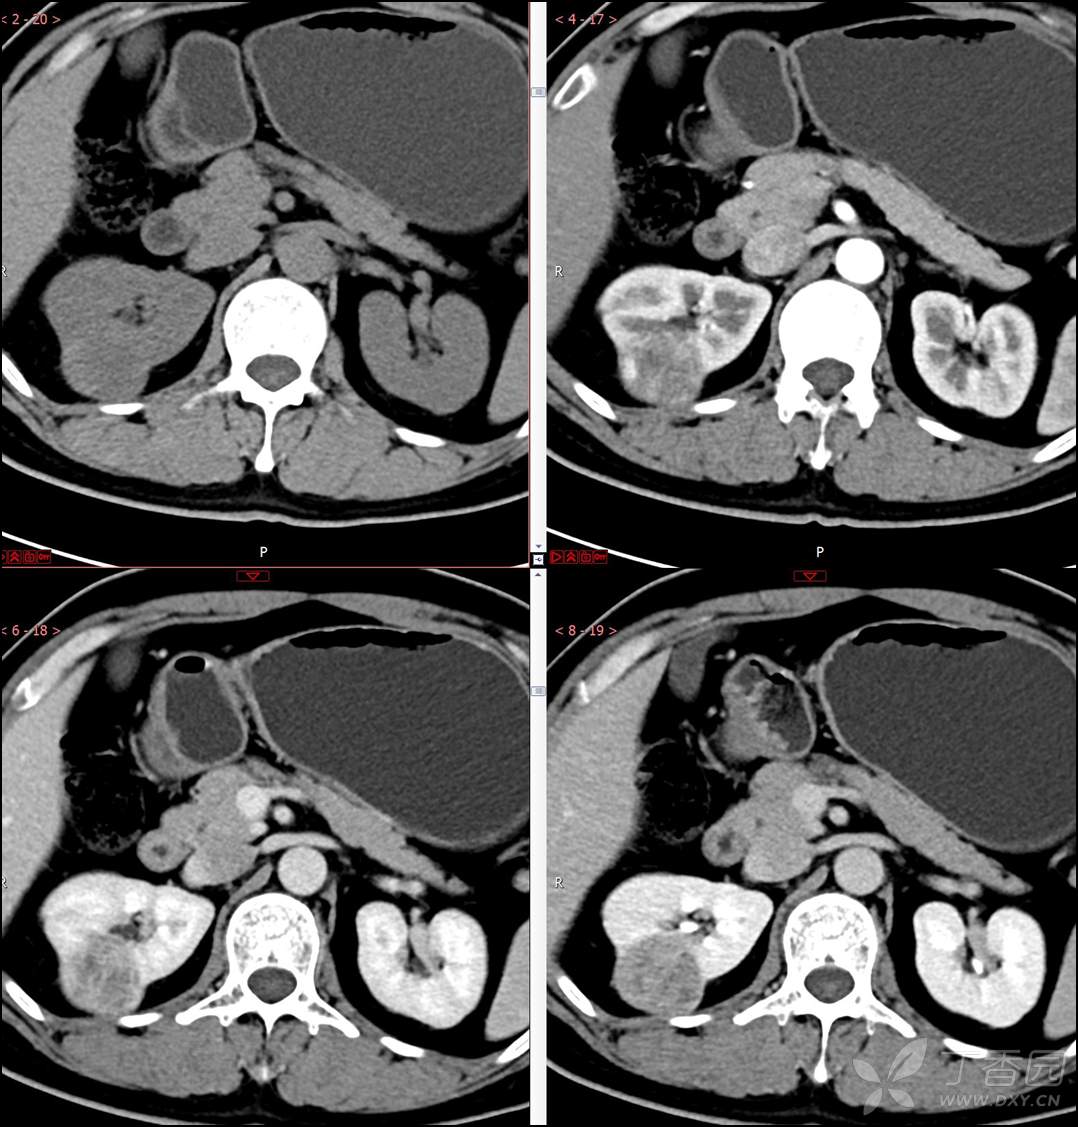

【影诊笔记518】中年男性,查体发现肾脏占位~『回复即可显示答案』

患者年龄:40岁

主诉:查体发现右肾肿物2月余

简要病史:患者2月余前于我院行健康查体,胸部(肺)CT平扫示:右肺中叶结节并右侧阻塞性肺炎;左肺上叶小结节;右肾占位。自诉无腰背部疼痛不适,无尿频、尿急、尿痛,无肉眼血尿,无恶心呕吐,无心悸、胸闷,无发热、寒战等不适,建议进一步检查。现患者为求进一步诊治于为我院就诊,建议手术治疗,门诊遂以“肾肿物(右)”收入院。患者自发病以来神志清,精神可,饮食可,睡眠欠佳,大便正常,体重近期无明显增减。